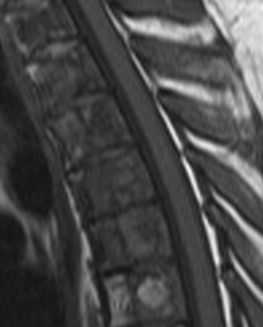

(Справа) STIR МР-И, сагиттальная проекция: признаки тяжелого спондилеза шейного отдела позвоночника, сопровождающего сужение субарахноидального пространства на нескольких уровнях, изменением Т2-сигнала спинного мозга на уровне С4-С5 Случайной находкой здесь стал врожденный блок С6-С7 позвонков. (Слева) На сагиттальном STIR МР-И позади зубовидного отростка виден характеризующийся низкой интенсивностью сигнала дегенеративный псевдопаннус, вызывающий компрессию передней камеры дурального мешка и вентральной поверхности спинного мозга. Также видны признаки диффузного дегенеративного поражения межпозвонковых дисков субаксиальных позвоночных сегментов с формированием блока на уровне С5-С6.

(Справа) Т2-ВИ, сагиттальный срез: признаки многоуровневого спондилеза шейного отдела позвоночника, наиболее выраженные на уровнях С5-С6 и С6-С7. На обоих этих уровнях отмечается центральный стеноз спинномозгового канала, вызванный протрузиями дисков и спондилофитами, деформирующими вентральную поверхность дурального мешка. На уровне С6-С7 в толще спинного мозга виден фокус миеломаляции.